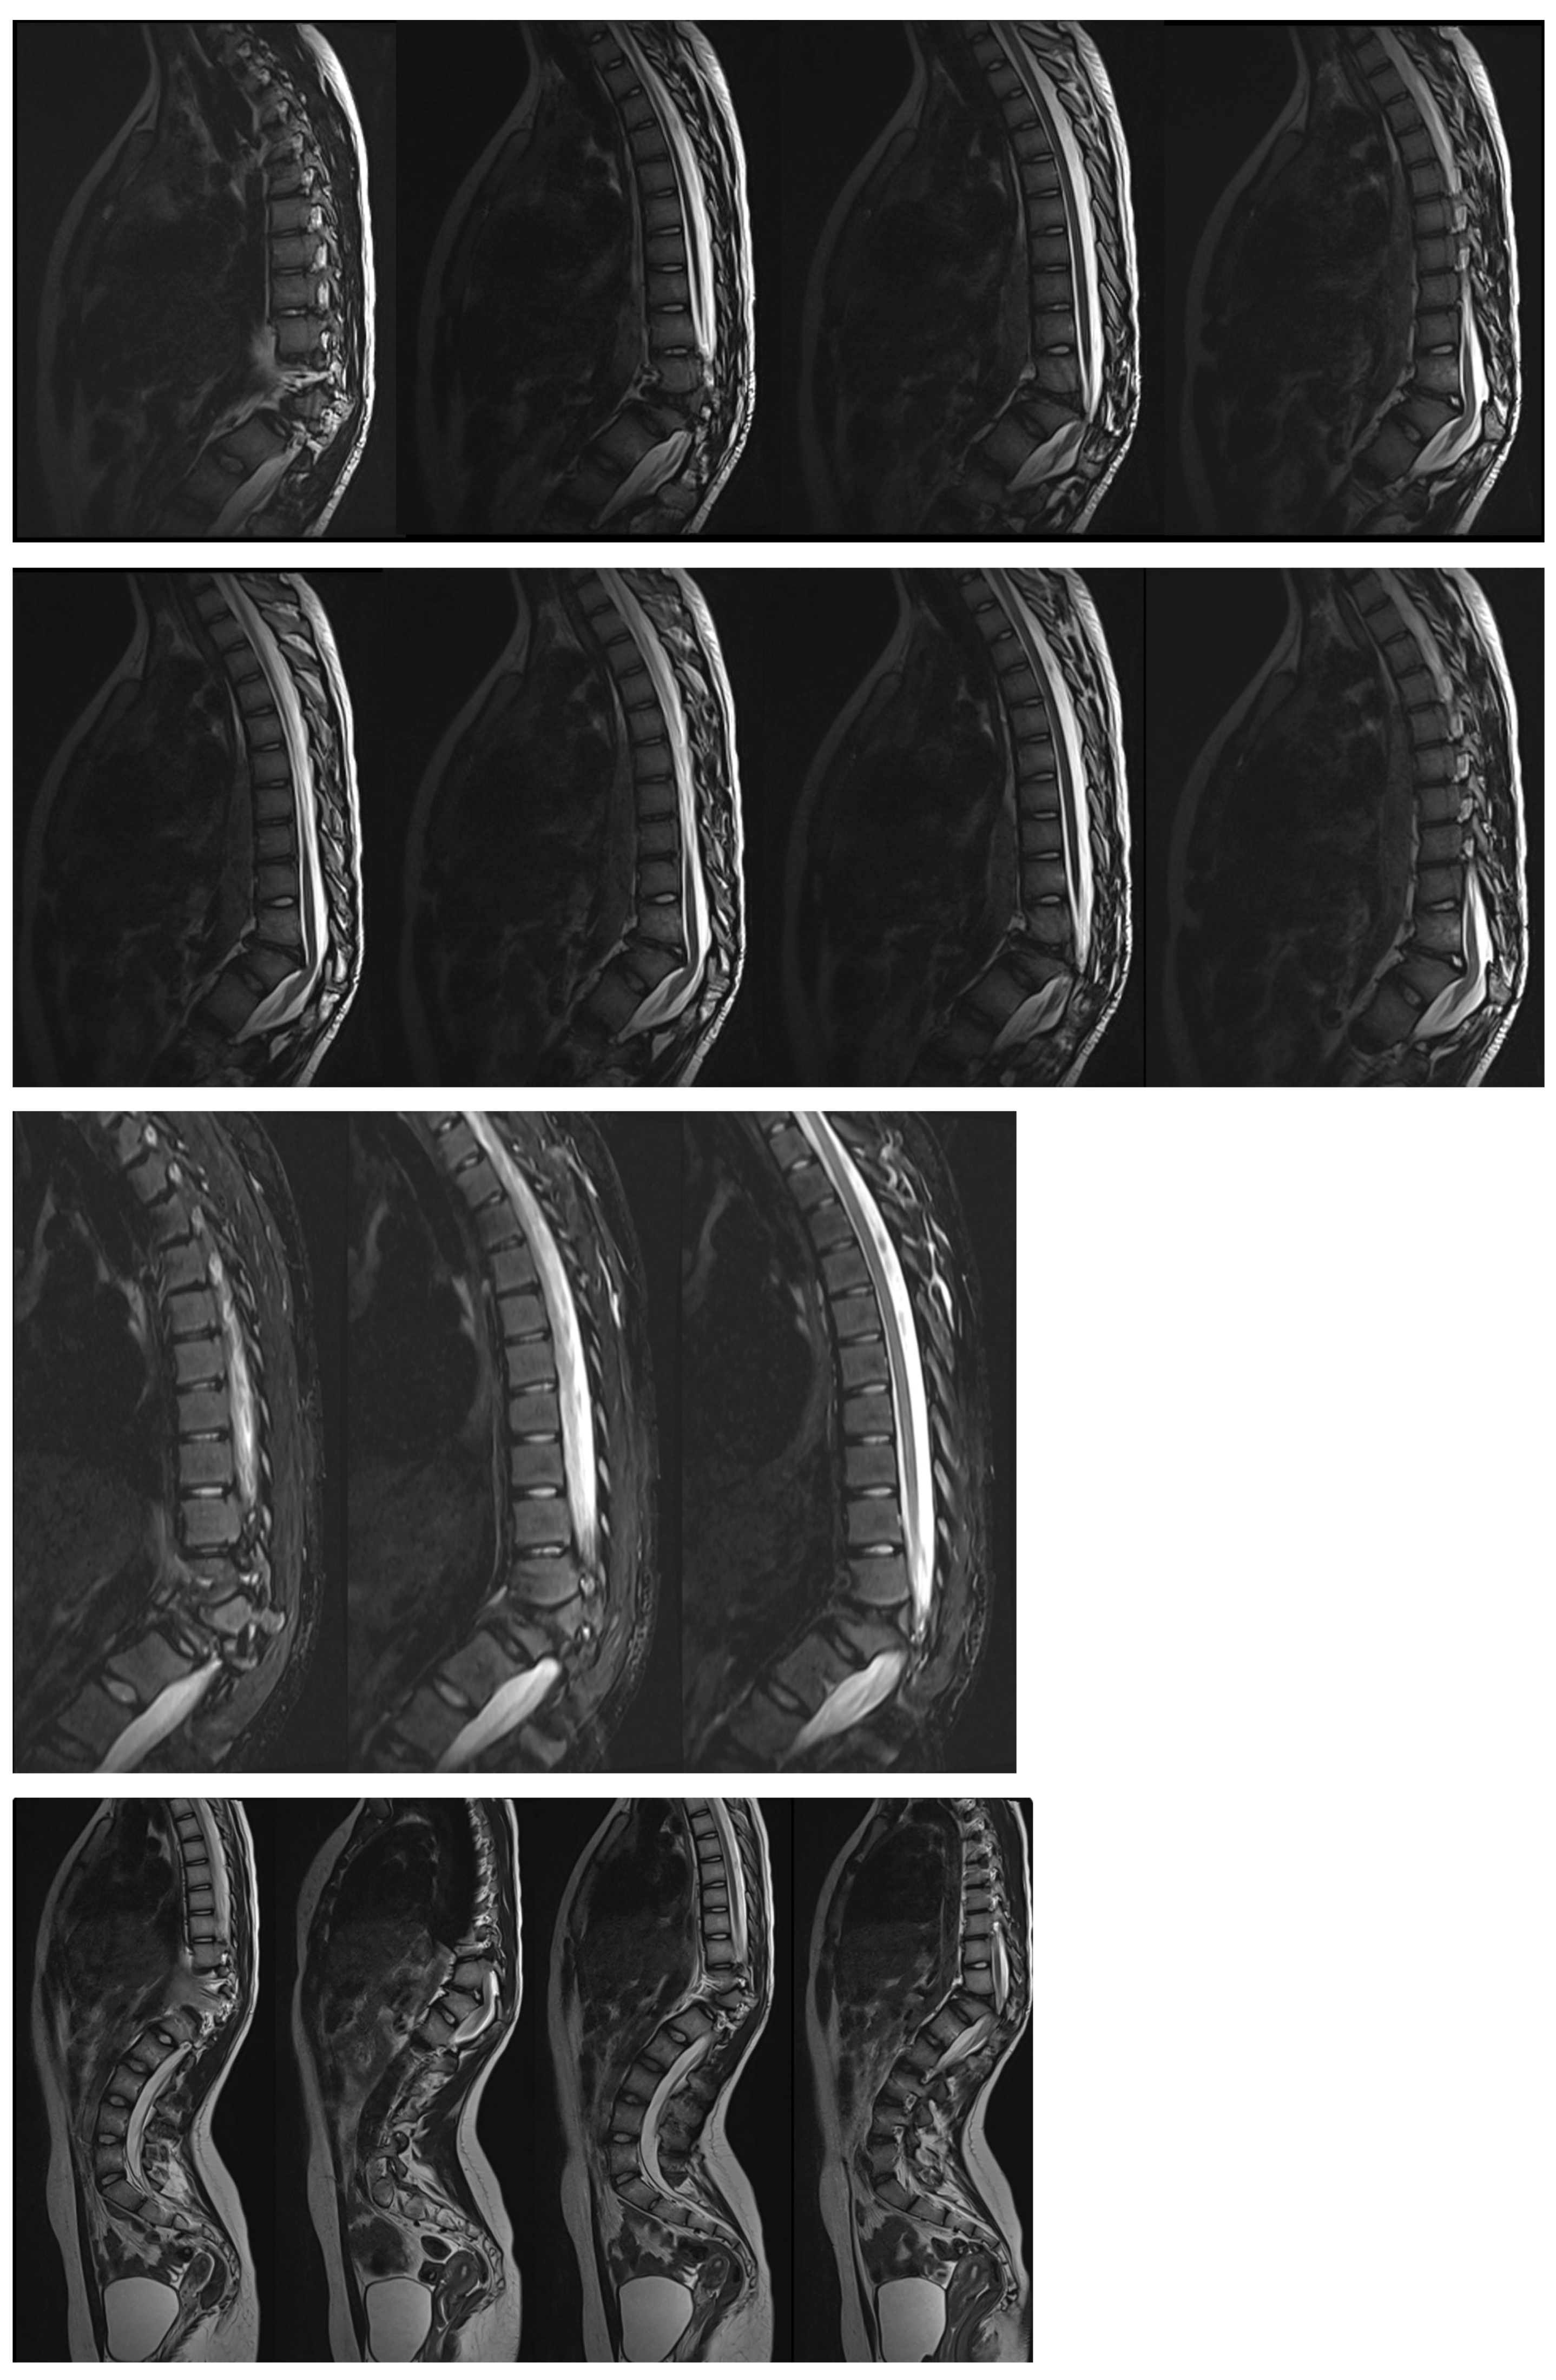

The obtained MRI of the thoracic and lumbar spine showed compression of the spinal cord at T10–T12 (Figure 3).

Figure 3. MRI scans showed spinal cord compression in the 16-year-old female before surgical treatment.